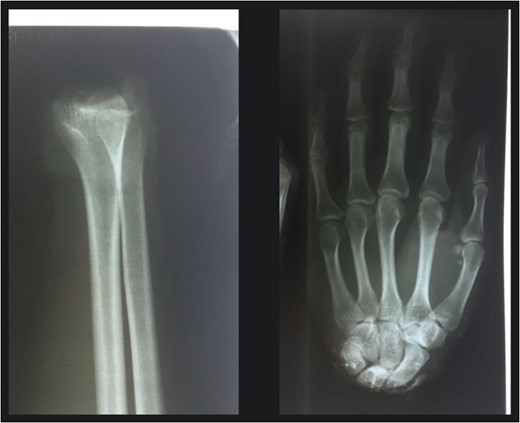

Patient was assaulted with a large knife (‘machete’), and while the assailant was trying to hurt his face, patient defended himself with his left hand and received the full force of the hit in his arm, cutting of the left hand. Relatives who were with the individual at the time placed the hand in a plastic bag, and the plastic bag in ice, transporting the patient and the hand to Hospital Roosevelt (Fig. 1).